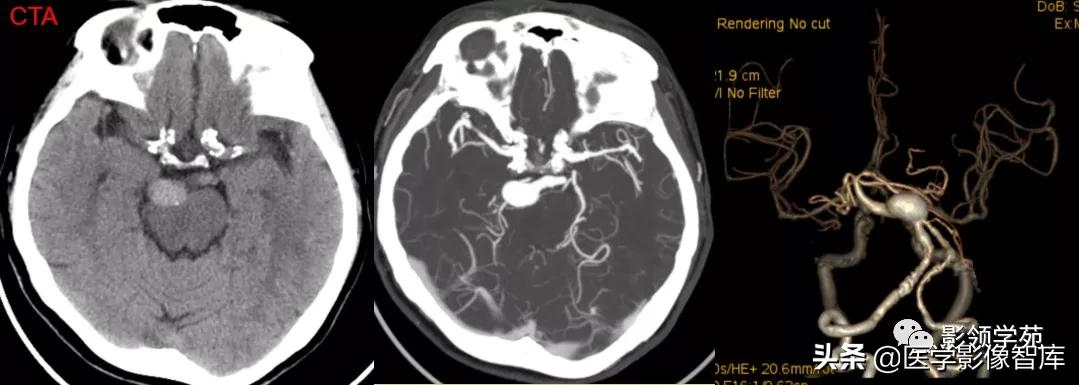

女 72岁,发现糖尿病3年余

鞍上区见一团块状稍高密度影,边界尚清,密度均匀。

鞍上右上方见一类椭圆形流空影。

病灶明显强化(瘤内血栓未强化),边界清楚,与右侧颈内动脉海绵段分界不清。垂体大小、形态未见异常。